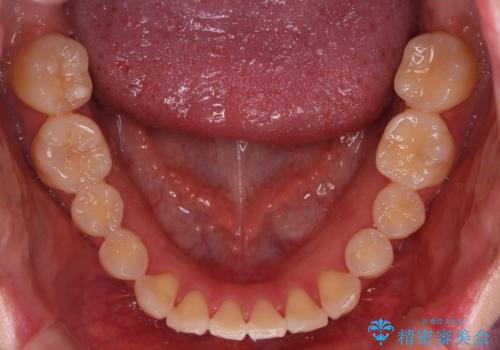

最初は、一番後ろの奥歯でしか噛んでいない状態で、上下の前歯の先端がちょうど当たる切端咬合でした。

口腔習癖の改善及び、ワイヤー矯正にて歯列の平坦化を行うことで咬合を確立することができました。

保定中の後戻りを防ぐため、口腔習癖の改善が必要です。